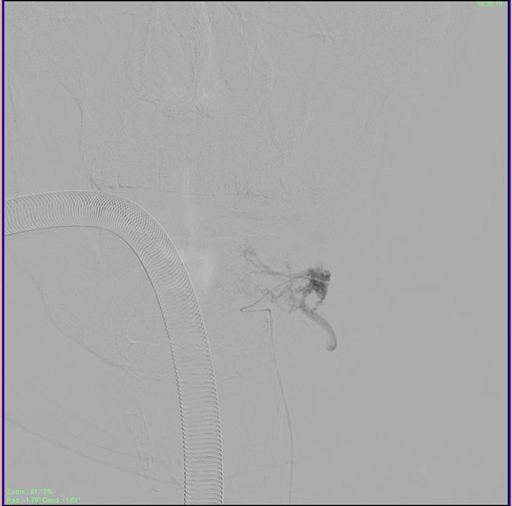

A 62-year-old male presented with right hemiparesis along with numbness and paresthesia over the right half of the body for 8 months. The symptoms began suddenly 8 months ago and gradually improved. His main complaint now was the spasticity along with increased frequency and hesitancy of urine. On examination at the outpatient clinic, he was found to have MRC (Medical Research Council) grade 4 power in his right upper and lower limb with spasticity of Ashworth grade 3, as well as decreased sensation over the right supraclavicular region and over the right shoulder. The patient was then investigated for the cause of his myelopathy with a Magnetic Resonance Imaging (MRI) of his cervical spine and brain. The MRI showed multiple flow voids epidurally, with a large draining vein at the craniovertebral junction entering the intradural space, compressing the cervical cord producing the resulting myelopathy (Figure 1A & B).

Figure 1A&1B MRI T2W images of the cervical spine showing the sagittal section of the compression of the cervical spinal cord secondary to large flow voids present inside and outside the dura.

The Axial image in figure 1b shows a large vessel compressing and displacing the cervical spinal cord with cord changes .